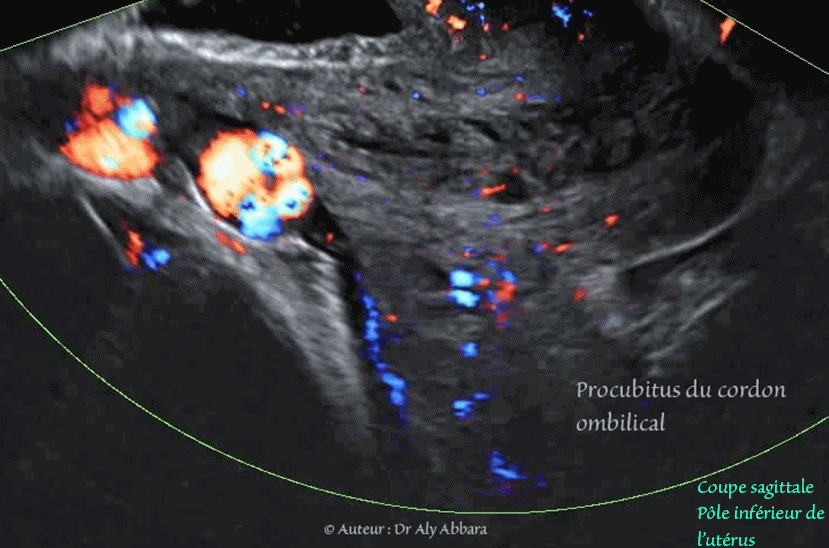

• Vidéo échographique en mode Doppler (Dynamic-Flow), à 37 SA, montrant un des aspects d'un procubitus du cordon (cordon ombilical praevia) : présence d'une anse du cordon ombilical au niveau du pôle inférieur de la cavité amniotique ; elle est coincée dans l'espace limité en haut, par le pôle céphalique foetal et en bas par la partie basse du segment inférieur de l'utérus ; cette anse funiculaire se trouve au contact avec l'orifice interne du col utérin.

Le positionnement de cette anse funiculaire dans cet espace est appelé procubitus du cordon) ; il s'accompagne d'un risque majeur de procidence du cordon ombilical au cours du travail, suite à la dilatation-effacement du col utérin et la rupture des membranes amniotiques.

Dans le cas présent : le procubitus du cordon ombilical était constant : la césarienne réalisée une semaine plus tard, pour une autre indication que ce cordon ombilical praevia, confirme le diagnostic : à l'hystérotomie segmentaire transversal, et l'ouverture des membranes amniotique, c'est cette anse funiculaire qui s'est dégagée immédiatement, en premier.